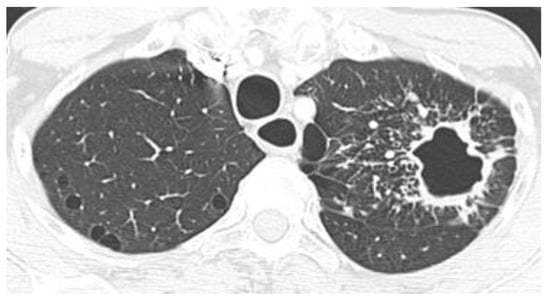

2.2. Non-Resolving Pneumonia

| Lung Nodule or Mass | Non-Resolving Pneumonia | Chronic Cavitating Disease | Disseminated Infection | Bronchiectasis & Asthma | |||||

| Imaging Clue | Dx | Imaging Clue | Dx | Imaging Clue | Dx | Imaging Clue | Dx | Imaging Clue | Dx |

| Adenopathy | Coccidioidomycosis Histoplasmosis | Consolidation + large nodules/masses | Blastomycosis Cryptococcosis Paracoccidioidomycosis | Grape-skin cavities + Lymphadenopathy | Coccidioidomycosis | Miliary ARDS Extrathoracic | ++ Histoplasmosis Coccidioidomycosis | High-attenuation mucus plugging Finger in glove | ABPA |

| Lung Mass | Cryptococcosis Blastomycosis | Adenopathy | Coccidioidomycosis Histoplasmosis | Calcified nodes | Histoplasmosis | ||||